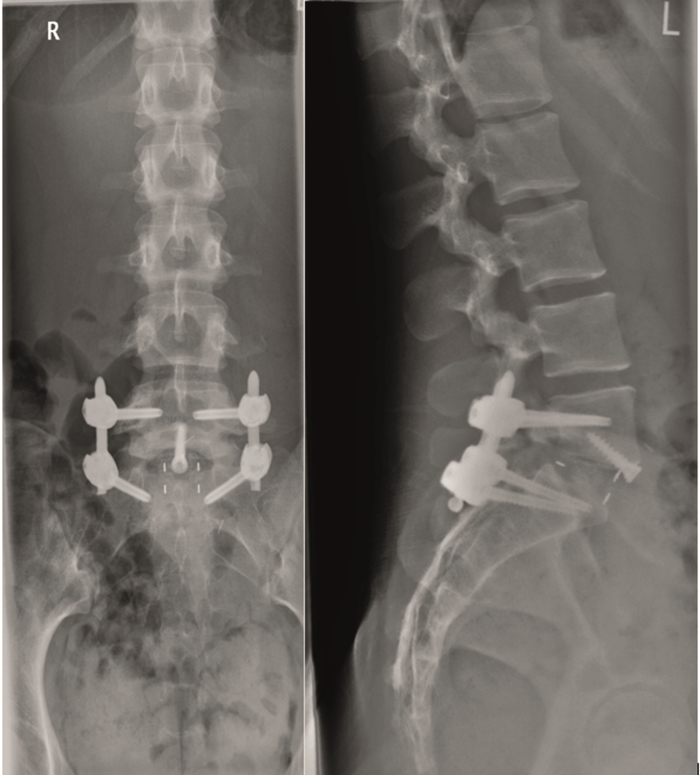

The patient underwent minimal access L5/S1 anterior interbody fusion with BMP followed by minimally invasive Matrix percutanous screw fixation (Fig 11).

The sagittal and axial T2-weighted MRI showed grade III disc degeneration with diffuse right-sided disc bulging (Fig 12).

The postsurgery AP and lateral images show stand-alone locked L5/S1 anterior fusion using Syncage Evolution with BMP-2 and an Aegis locking plate (Fig 13).